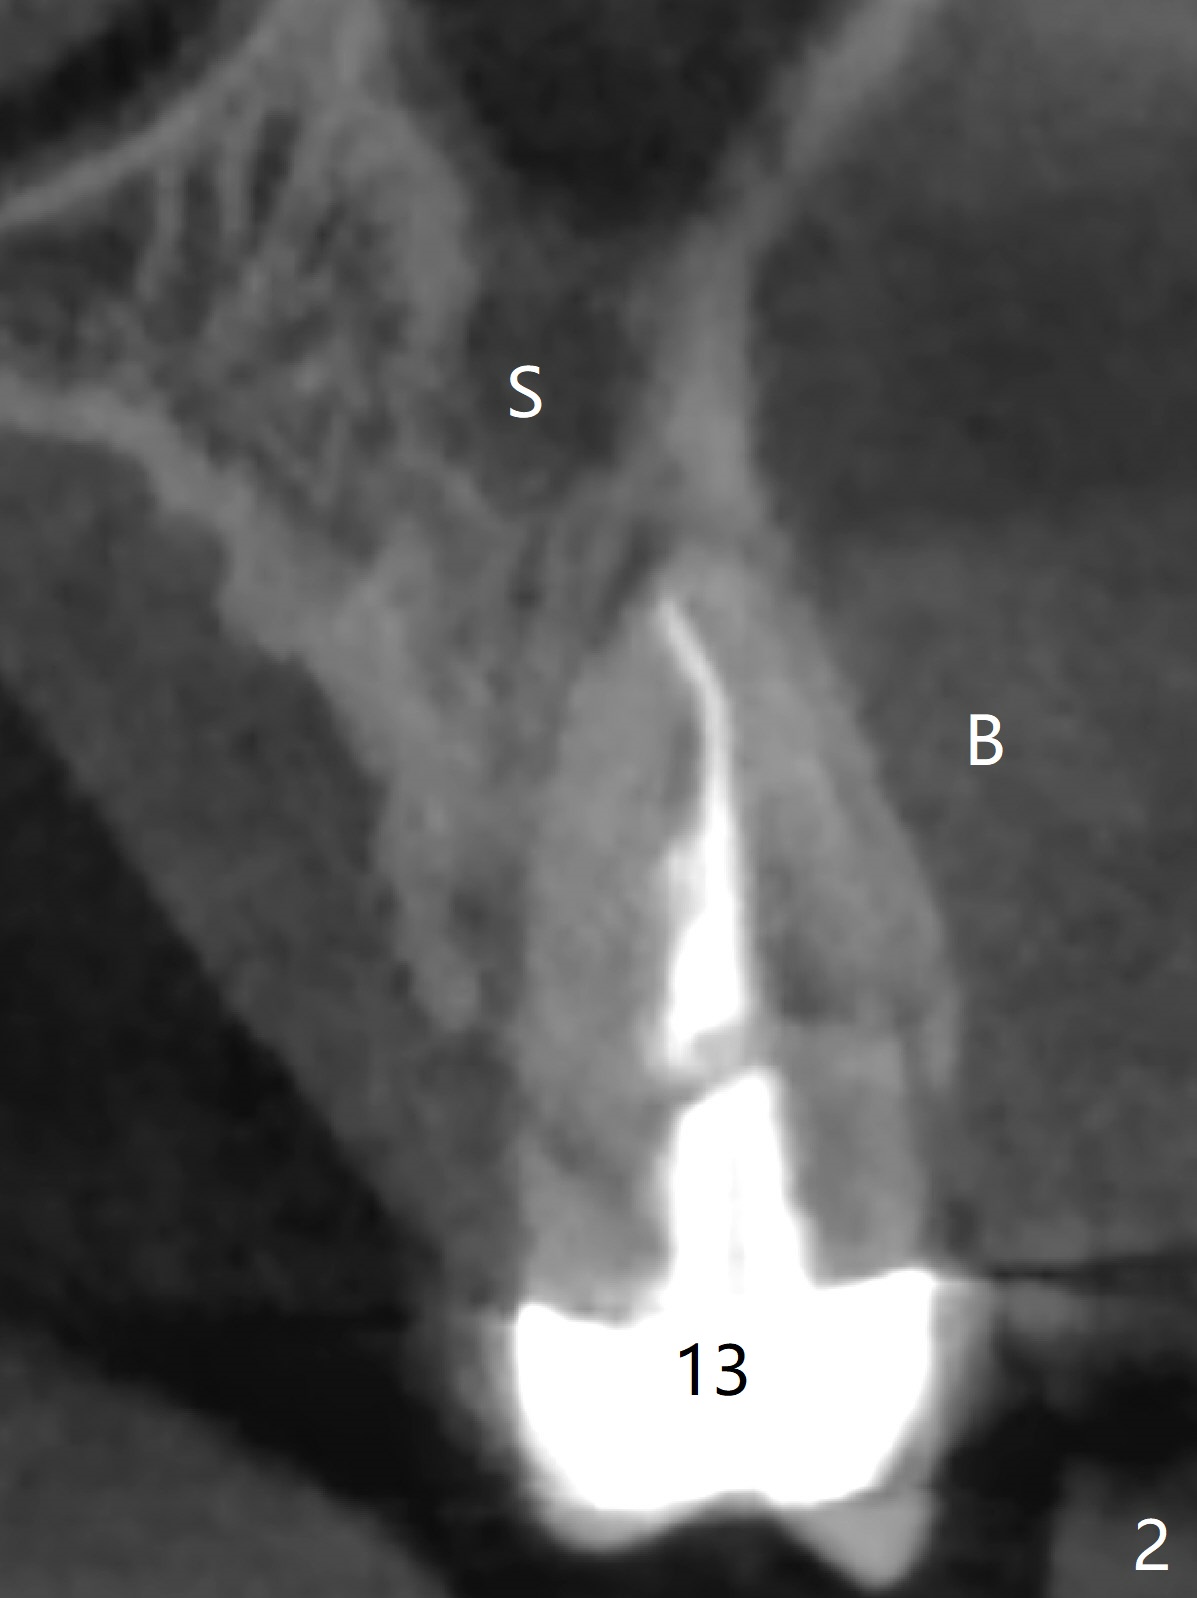

A 56-year-old man returns with chief complaint of a loose upper left tooth. Exam reveals fractured root (Fig.1 arrowheads). The apex is close to the sinus (Fig.2 (CT coronal section) S (B: buccal)). After extraction (Fig.3), start initial coronal osteotomy with a guide (Fig.4 red), ~ 1 mm from the sinus floor. Following sinus lift, PRF and bone graft (Fig.5 yellow circles), finish apical osteotomy and place a 4x15 mm implant (Fig.5,6). An angled abutment is expected (15 degree, Fig.5).